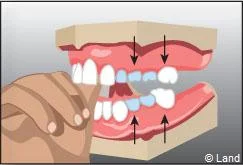

Lorsque des dents de lait ont été extraites trop tôt parce qu’elles étaient cariées, les dents de part et d’autre peuvent migrer et combler l’espace, bloquant ainsi l’éruption des dents définitives. Il est alors nécessaire de maintenir cet espace avec un appareillage spécifique appelé « mainteneur d’espace » jusqu’à l’évolution des dents définitives.